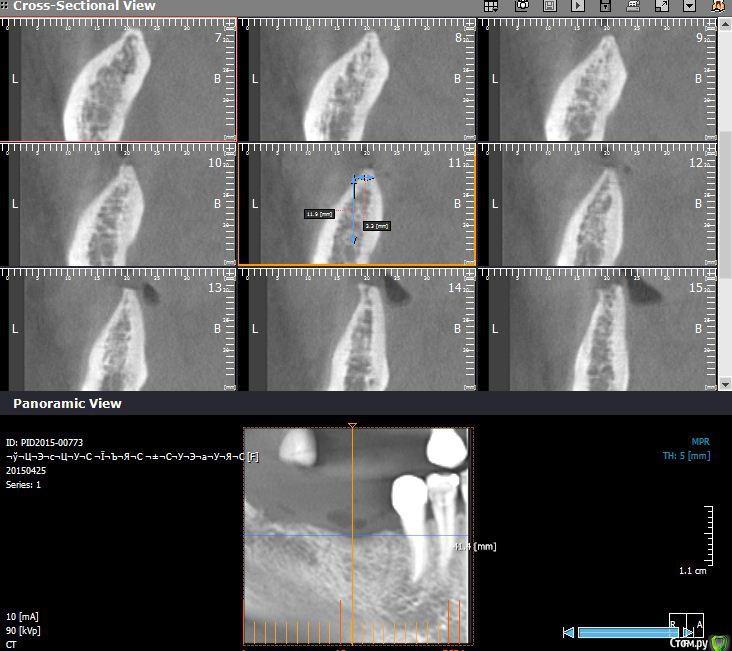

Endorphin Опубликовано 1 февраля, 2016 Автор Поделиться Опубликовано 1 февраля, 2016 Если возможно, то выкладывайте, пожалуйста КТ с измерениями в миллиметрах. А то совсем не понятно что там и как выросло. До аугментации. При такой форме не решился расщеплять. От вершины гребня до нерва не многим более 11 мм в среднем на протяжении дефекта. Ширина там, где хотелось бы видеть платформу 2-3мм. 5 месяцев после аугментации. Видно что частично графт скорее всего уйдет, так и вышло. Ширина 6.5мм, высота 12-13. немного не там где хотелось, но имплантация возможна. Контрольная кт после установки имплантатов. Dentium sl 3.8x10 3 Ссылка на комментарий